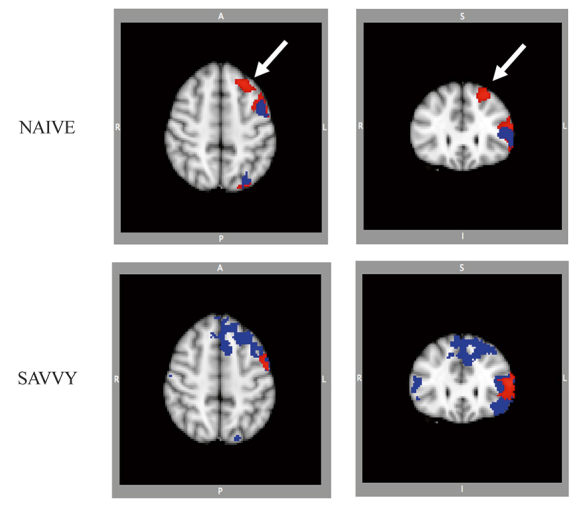

• 대상: 55~76세 성인 24명 (숙련자 12명, 비숙련자 12명).

• 텍스트 읽기: 양 그룹 모두 언어·기억·시각 영역이 비슷하게 활성화.

• 인터넷 검색: 비숙련자 → 읽기와 유사한 패턴.  / 숙련자 → 의사결정, 복잡한 추론, 해마 등 추가 영역까지 활성화, 총 활성화 부피 2배 이상.

• 의미: 인터넷 검색은 뇌를 자극하는 정신 운동이 될 수 있음.

• 반복 훈련 결과: 비숙련자 → 훈련 후 더 넓은 전두엽 네트워크 동원. / 숙련자 → 훈련 후 활성화 감소(효율적 반응).

인터넷에 익숙하지 않은 사람들과 인터넷에 익숙한 사람들의 훈련 전후 인터넷 검색 과제 활성화. 파란색은 기준선에서의 활성 영역을, 빨간색은 훈련 후 패턴을 나타냄.

훈련 전후의 중첩 영상을 통해 인터넷 경험이 없는 집단에서 훈련 후 전두엽 활성 증가를 확인할 수 있음

• 결론: 짧은 인터넷 훈련만으로도 중년·노년층 뇌 활동 패턴이 변화가능.